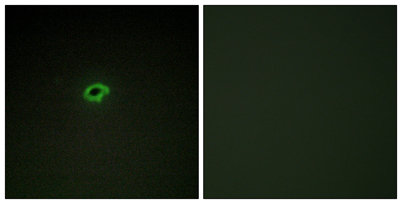

IF

Recomended Dilution Immunohistochemistry: 1/100 - 1/300. Immunofluorescence: 1/200 - 1/1000. ELISA: 1/5000. Not yet tested in other applications.